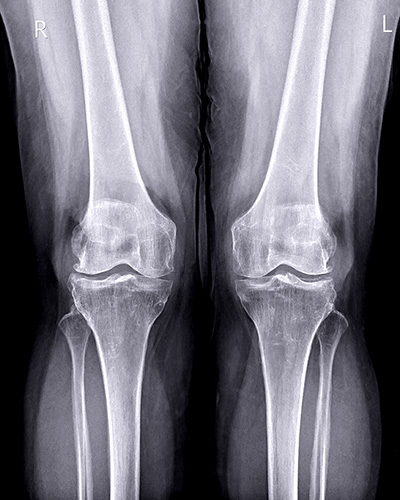

A artrose localizada em um dos compartimentos do joelho geralmente ocorre devido ao aumento da pressão sobre essa região específica da articulação. Diversos fatores podem contribuir para esse processo, entre eles:

• Alterações do eixo da perna de origem genética ou decorrentes de fraturas prévias.

• Meniscectomias extensas, que reduzem a proteção natural entre os ossos e aumentam a sobrecarga articular.

• Excesso de peso corporal e alterações ou fraqueza muscular.

Esses fatores levam à sobrecarga progressiva do compartimento afetado, favorecendo o desgaste da cartilagem.

Com a progressão da artrose, a alteração do eixo do joelho tende a se acentuar, podendo comprometer outros compartimentos da articulação. O sintoma mais comum é a dor localizada, geralmente no lado interno ou externo do joelho, de acordo com o compartimento afetado.